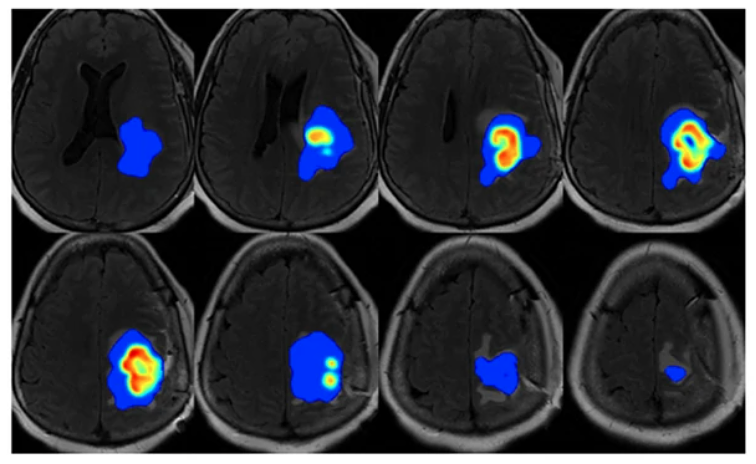

Forecasting response of high-grade glioma patients to radiation therapy

Image-based personalization of computational models for predicting response of high-grade glioma to chemoradiation

D. Hormuth, K. A. Al Feghali, A. Elliott, T. Yankeelov, C. Chung